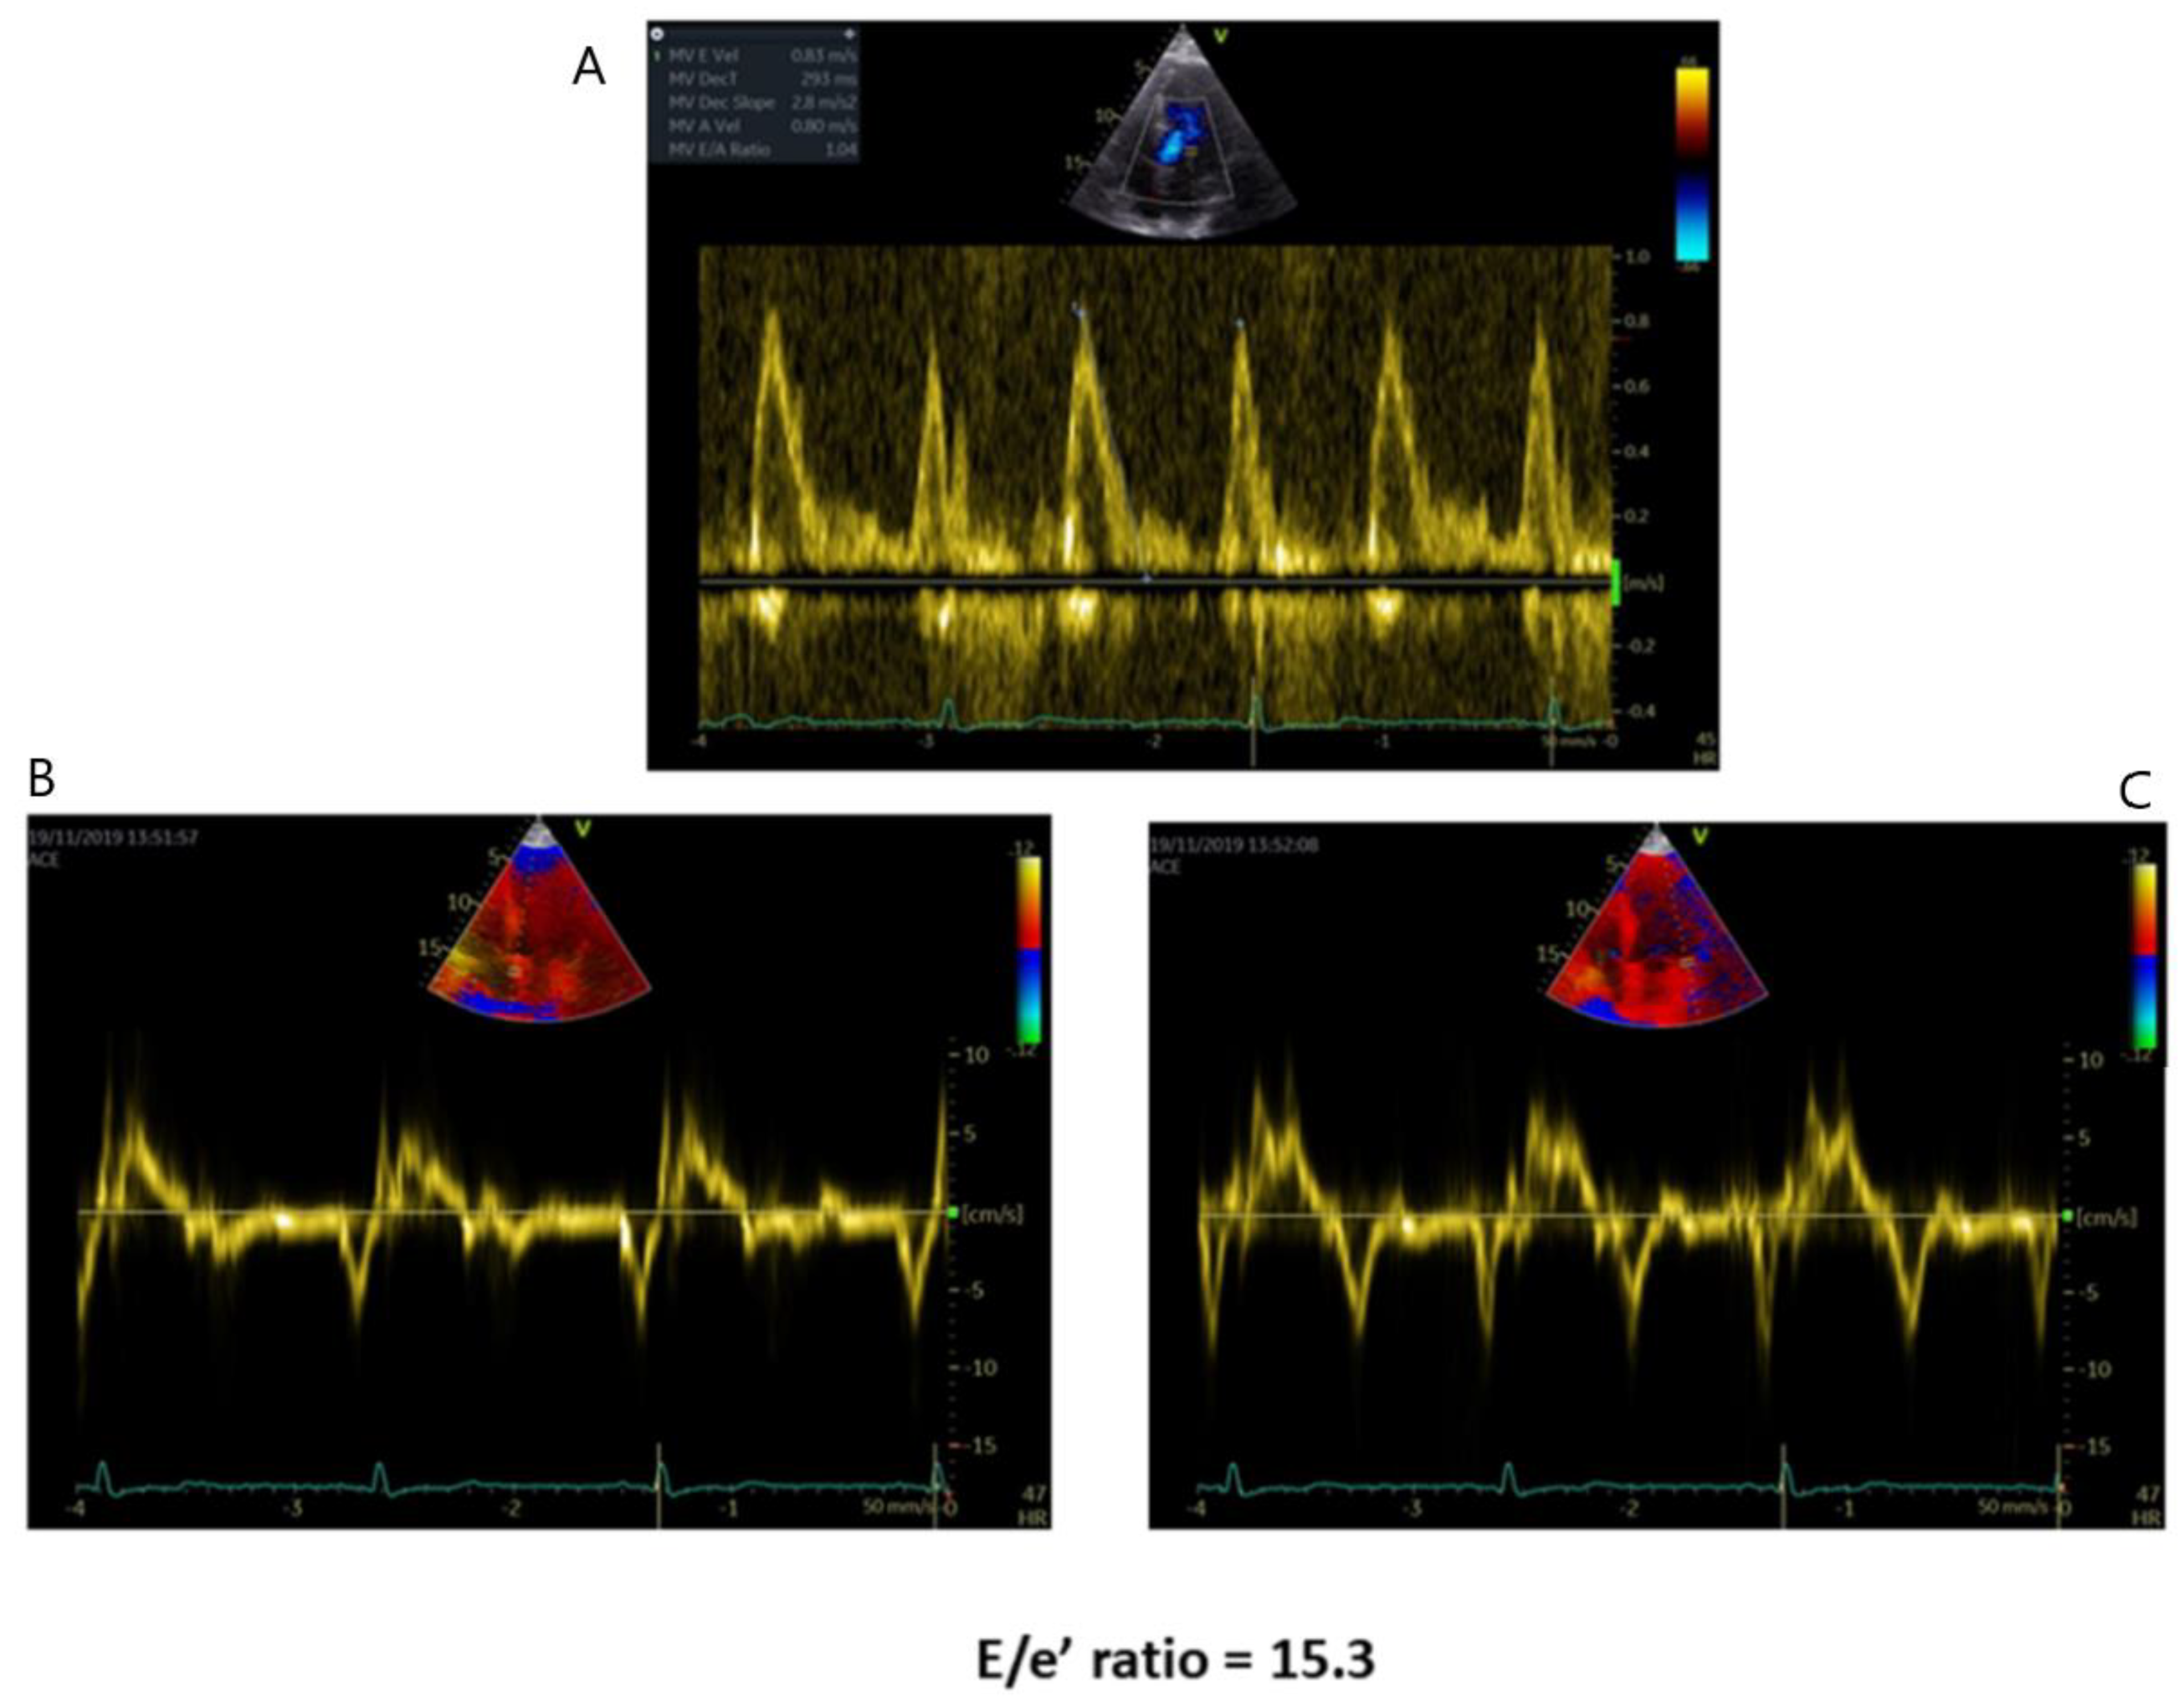

- Palecek, T.; Linhart, A.; Lubanda, J.C.; Magage, S.; Karetova, D.; Bultas, J.; Aschermann, M. Early diastolic mitral annular velocity and color M-mode flow propagation velocity in the evaluation of left ventricular diastolic function in patients with Fabry disease. Heart Vessels. 2006, 21, 13–19. [Google Scholar] [CrossRef]

- Pieroni, M.; Chimenti, C.; Ricci, R.; Sale, P.; Russo, M.A.; Frustaci, A. Early detection of Fabry cardiomyopathy by tissue Doppler imaging. Circulation 2003, 107, 1978–1984. [Google Scholar] [CrossRef] [PubMed]

- Zamorano, J.; Serra, V.; Pérez de Isla, L.; Feltes, G.; Calli, A.; Barbado, F.J.; Torras, J.; Hernandez, S.; Herrera, J.; Herrero, J.A.; et al. Usefulness of tissue Doppler on early detection of cardiac disease in Fabry patients and potential role of enzyme replacement therapy (ERT) for avoiding progression of disease. Eur. J. Echocardiogr. 2011, 12, 671–677. [Google Scholar] [CrossRef]

- Liu, D.; Oder, D.; Salinger, T.; Hu, K.; Müntze, J.; Weidemann, F.; Herrmann, S.; Ertl, G.; Wanner, C.; Frantz, S.; et al. Association and diagnostic utility of diastolic dysfunction and myocardial fibrosis in patients with Fabry disease. Open Heart 2018, 5, e000803. [Google Scholar] [CrossRef] [PubMed]

| Diastolic Dysfunction | -Mitral flow Doppler parameters alteration -E/e’ ratio increase -LA dilation | -In AFD patients with LV hypertrophy, diastolic dysfunction underlies the symptoms of heart failure |